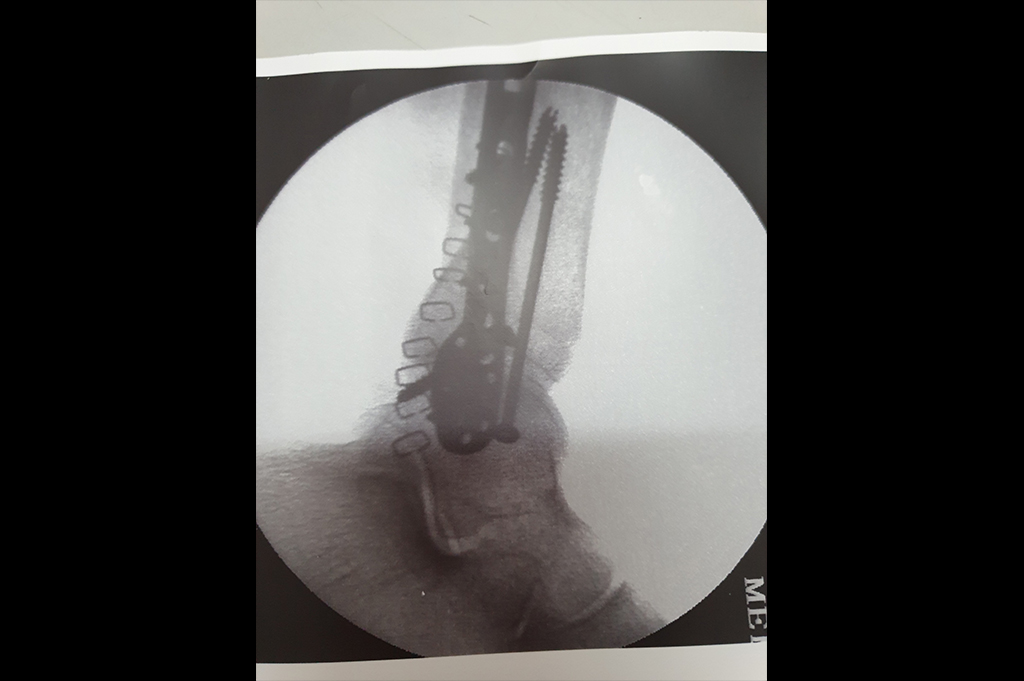

Subtrochanteric Fracture